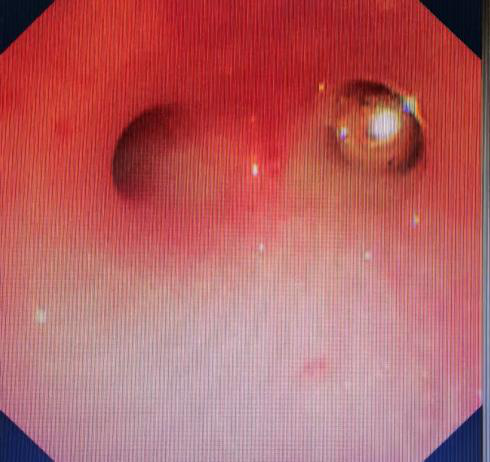

多学科团队面临严峻挑战:通过支气管镜下所见患儿声门水肿,金属珠子表面光滑,稍有不慎都有可能滑落再次阻塞气道。麻醉团队通过精准镇静,呼吸三科内镜团队娴熟操作支气管镜,在视野狭窄的气道内通过异物网篮成功将金属珠完整取出!术后患儿生命体征平稳,转入PICU进一步观察。